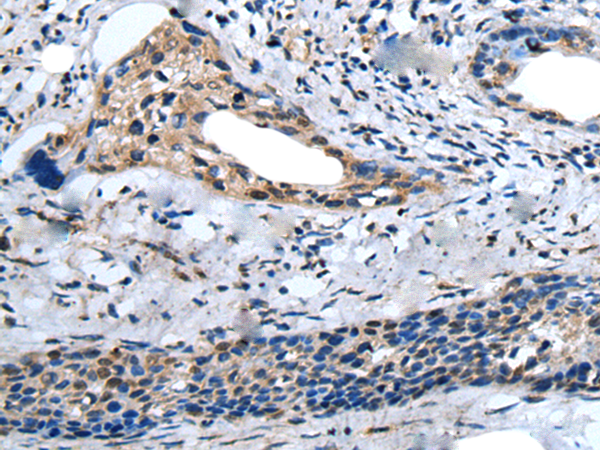

IHC positive control:

Human lung cancer and human cervical cancer

IHC Recommend dilution:

25-100